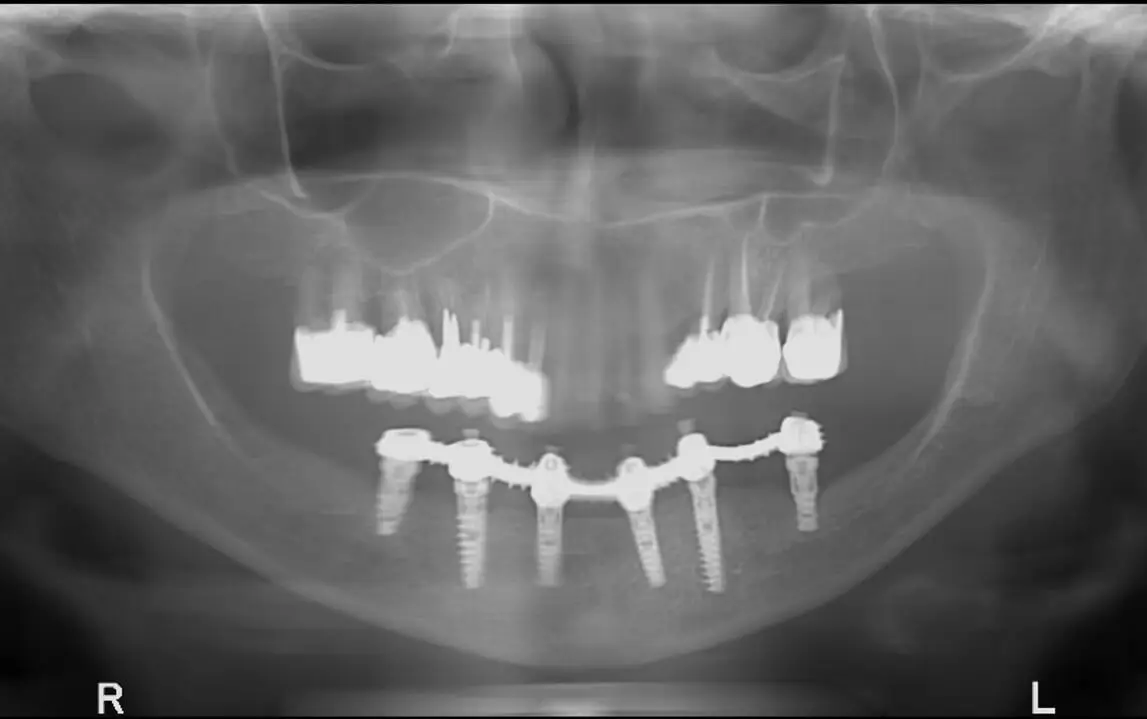

Даже в сложных случаях: имплантация зубов за один день.

Наша стоматологическая клиника в Иерусалиме является одной из трёх клиник доктора Балана, разбросанных по всей стране. Две другие – Тель-Авивская клиника имплантации и наша флагманская клиника в Кирьят-Яме. Как и во всех остальных наших клиниках, в клинике доктора Балана в Иерусалиме также проводятся имплантации зубов за один день, причём даже в наиболее сложных ситуациях.

• Имплантация в верхней, нижней или обеих челюстях.

• Скуловая имплантация в условиях отсутствия кости нижней челюсти.

• Базальная имплантация при отсутствии кости верхней челюсти.

• Повторная имплантация в случаях неудачи предыдущей имплантации.